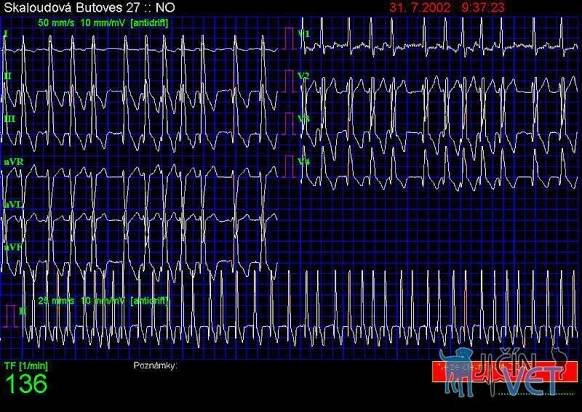

Obr.1 ( EKG 1) – Fibrilace síní patrná ve všech svodech.

Fibrilace síní může na EKG vypadat různě. Může být přítomna tachykardie, bradykardie či normální frekvence. Důležitá je nepravidelnost rytmu, tj. QRS komplexy jsou od sebe různě daleko.